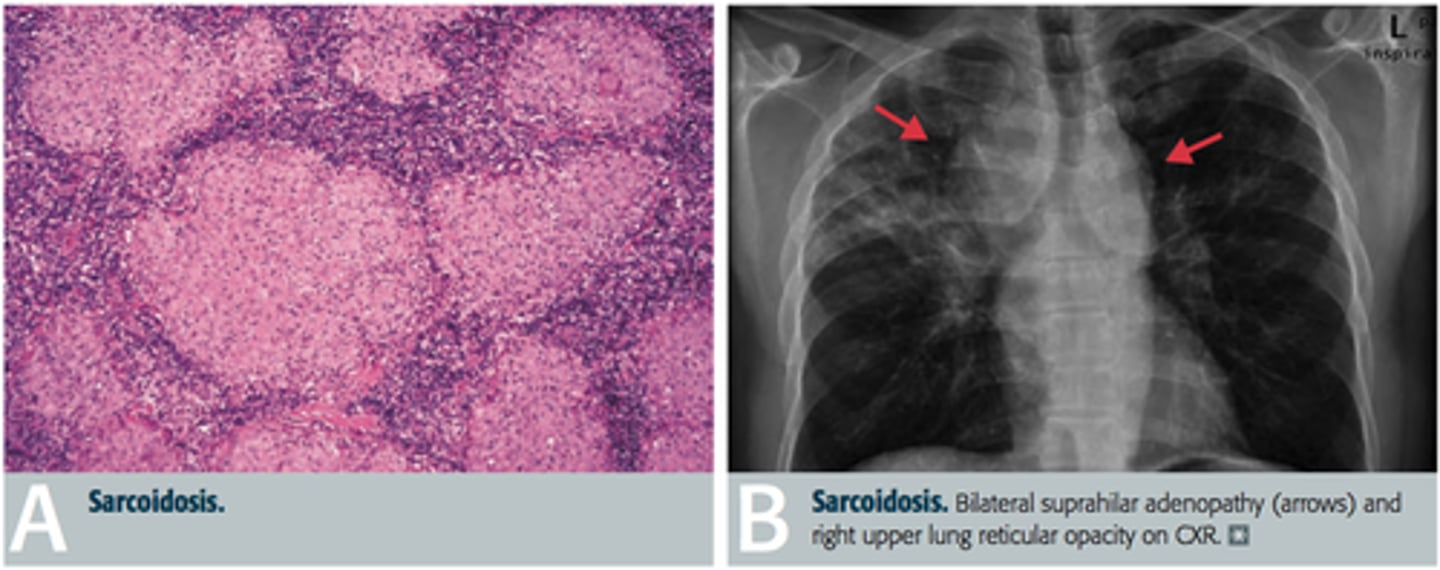

what auto-immune salivary gland lesion is a multisystem, granulomatous disorder of unknown cause?

sarcoidosis

what auto-immune salivary gland lesion is caused by the improper degradation of unknown antigenic material?

what auto-immune salivary gland lesion forms a noncaseating granulomatous inflammation in various organs of the body and is 10-17 times more common in African Americans?

what auto-immune salivary gland lesion is associated with lupus pernio (violaceuous, indurated lesions frequent in the nose, ears, lips and face)?

what auto-immune salivary gland lesion sometimes involves the lacrimal glands leading to xerophthalmia?

what auto-immune salivary gland lesion can cause salivary gland enlargement and leads to xerostomia (mimicking Sjogren syndrome)?

what auto-immune salivary gland lesion has oral manifestations (other than salivary gland involvement) like masses, papules, and ulcerations?

what auto-immune salivary gland lesion forms lesions that may be brown-red, violaceous (violet), or hyperkeratotic in the oral cavity?

what auto-immune salivary gland lesion is diagnosed via negative findings for special stains and microorganisms, elevated ACE levels, and treated with corticosteroids?